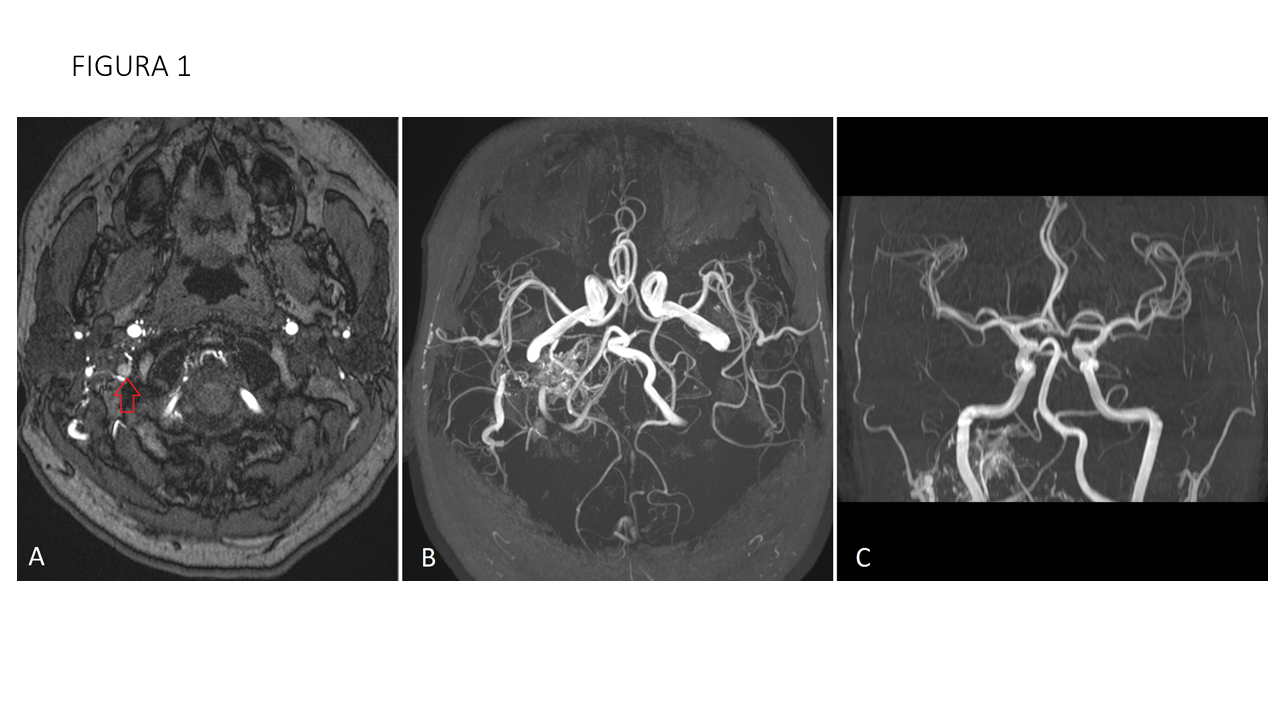

FIGURA 1 Secuencia TOF en plano axial (A y B) y coronal (C) muestran múltiples vasos de pequeño calibre en peñasco derecho, con arterialización de vena yugular interna derecha (flecha roja).